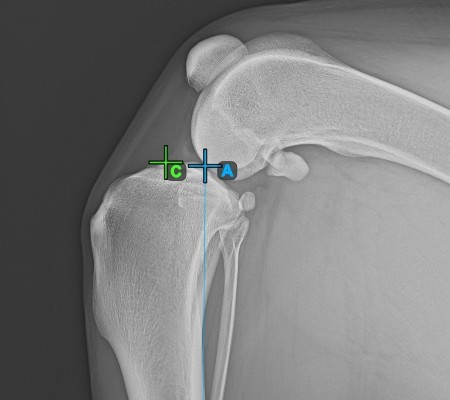

Miután azonosította a tibia hosszanti tengelyét, jelölje meg a tibia fejének (tibia plató) legfelső pontját.

A lenti kép a tibia plató legfelső pontjának szokásos elhelyezkedését ábrázolja.